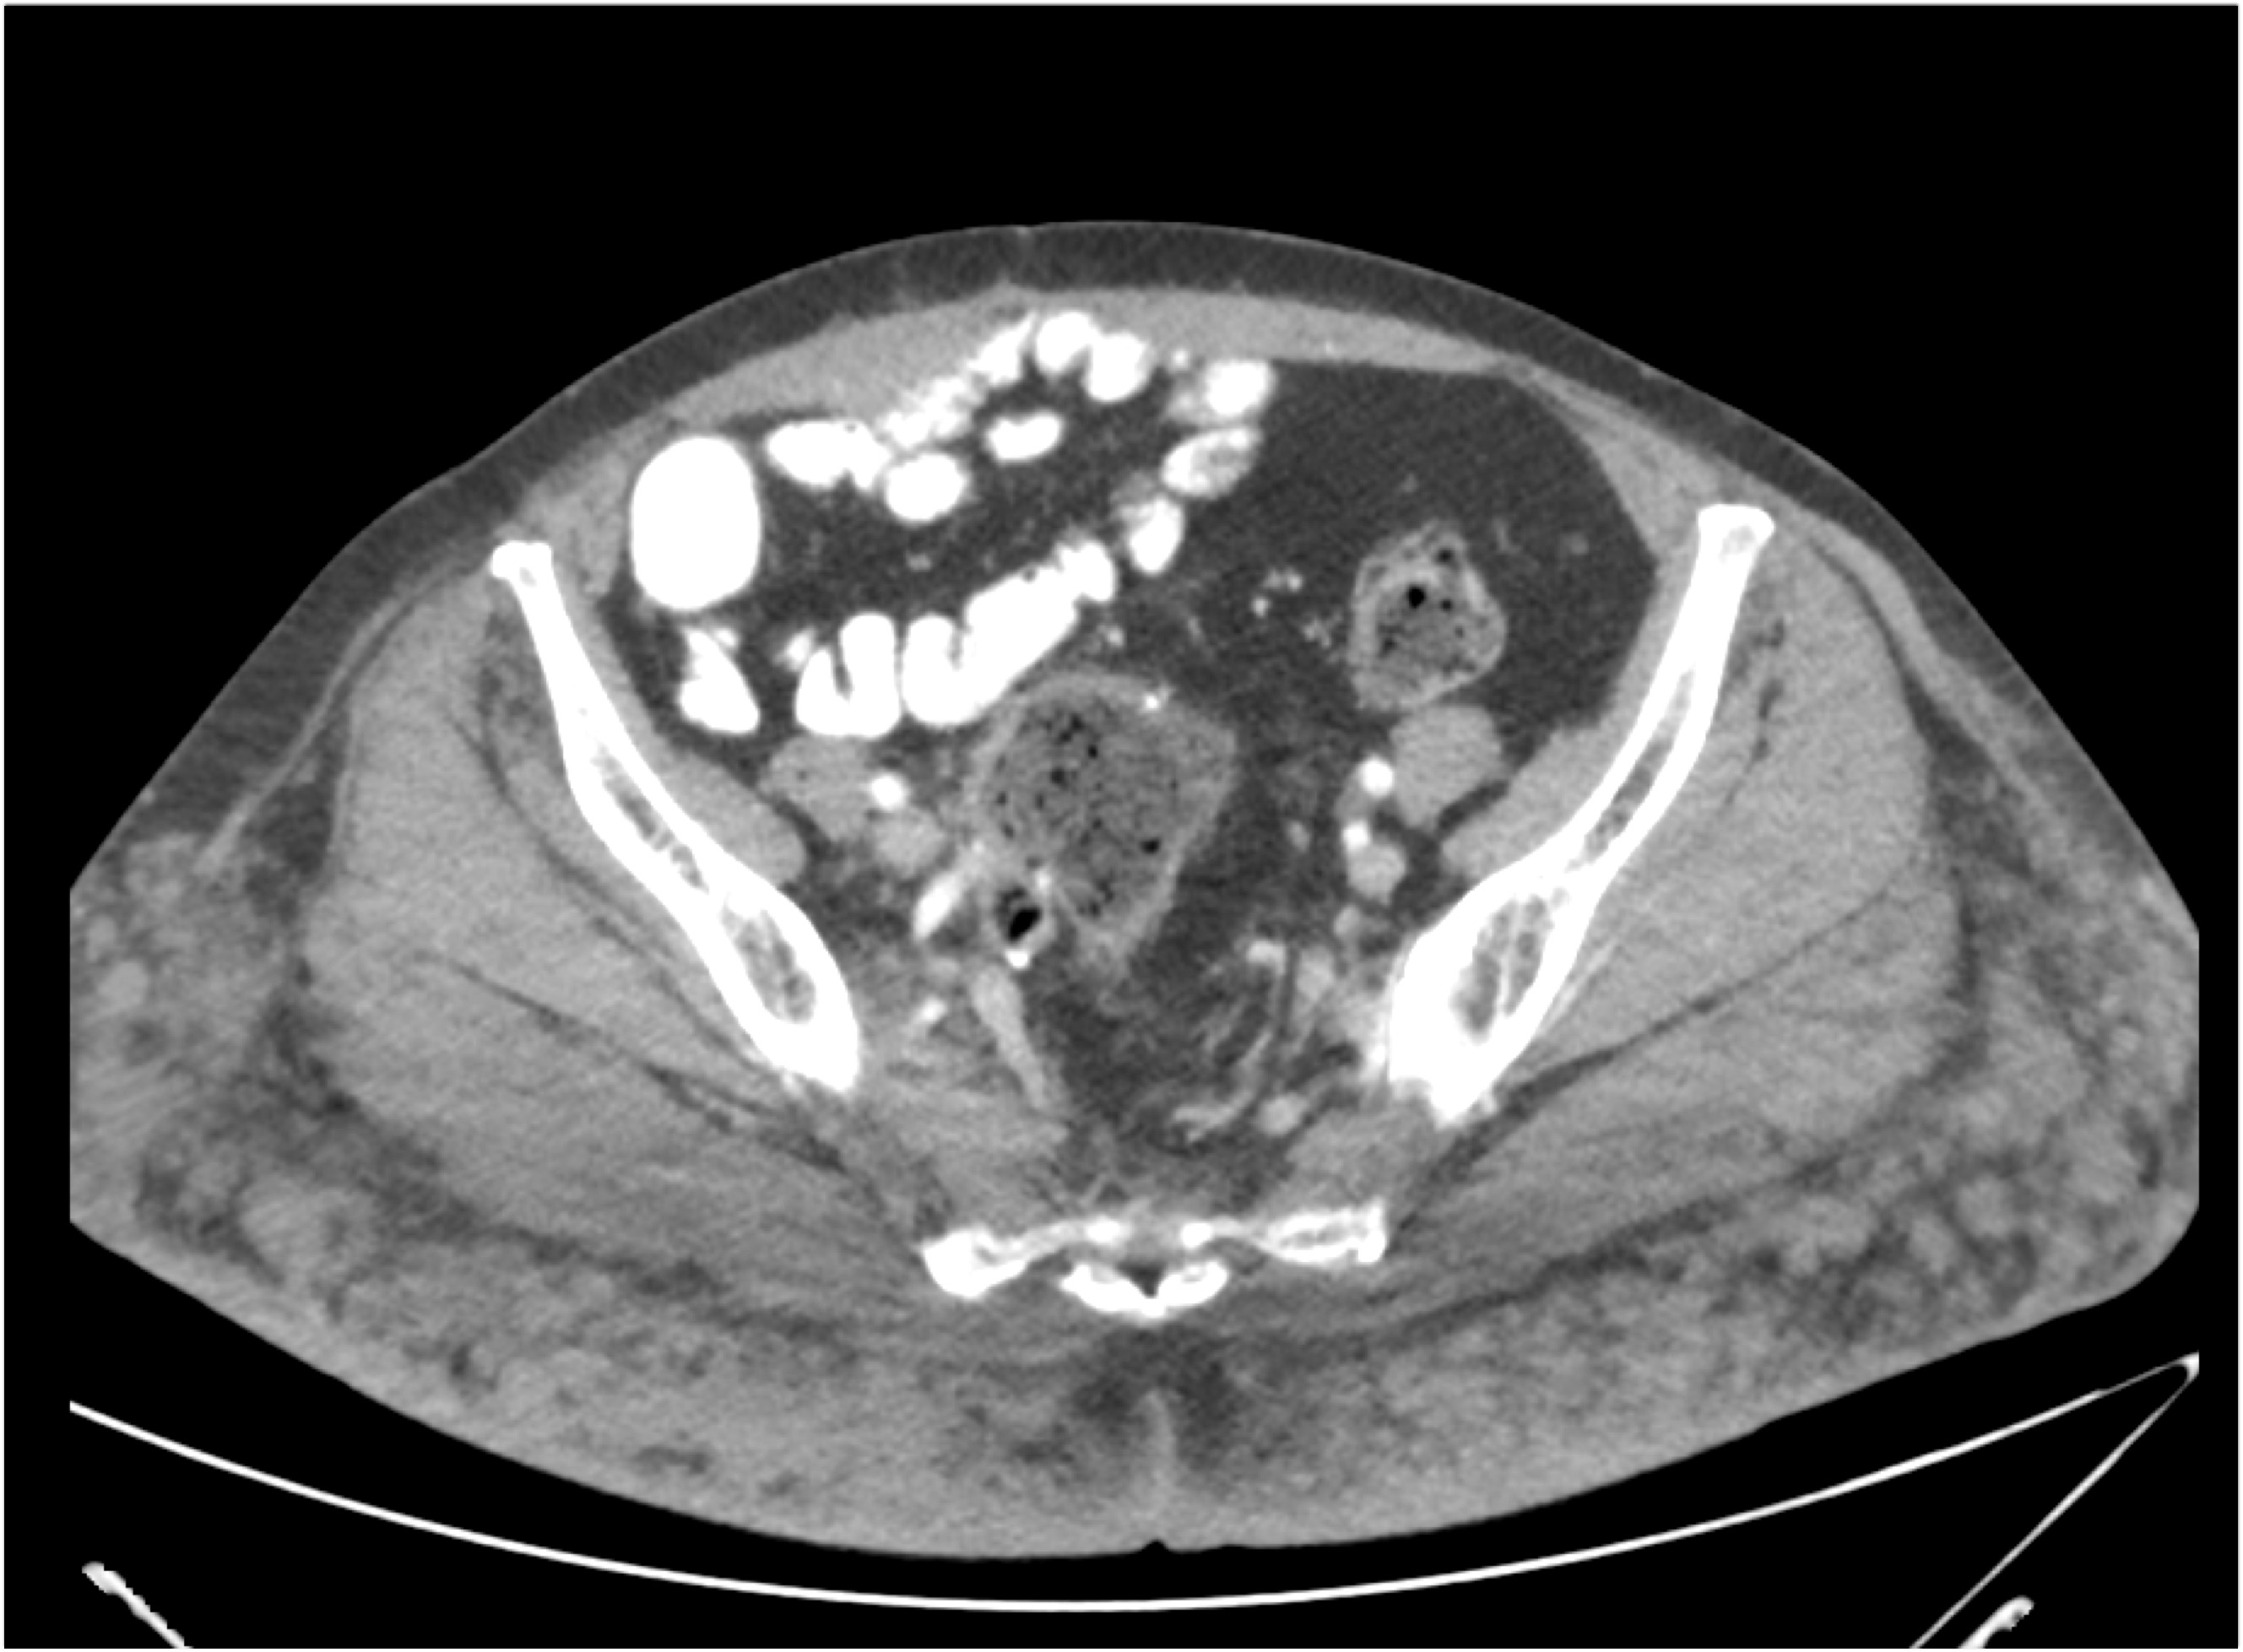

1) The most likely diagnosis for this mass is?

bladder leiomyoma

bladder sarcoma

duplication cyst

implant of ovarian tissue